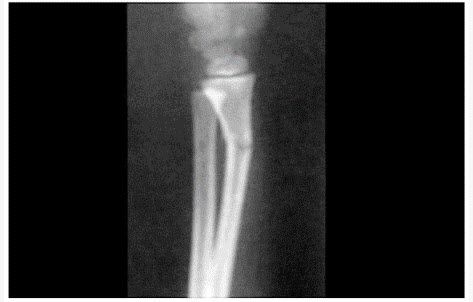

青枝骨折图片,青枝骨折

治疗(一)山西白求恩医院骨科整复室 写美篇对于小孩尺桡骨青枝骨折

似见横形透亮线影,且见骨皮质欠光整 诊断意见:右侧桡骨远端青枝骨折

左尺桡骨折青枝骨折

ofeslh:之所以提到尺骨,其实有以下原因: 1,尺骨其实已存在青枝骨折